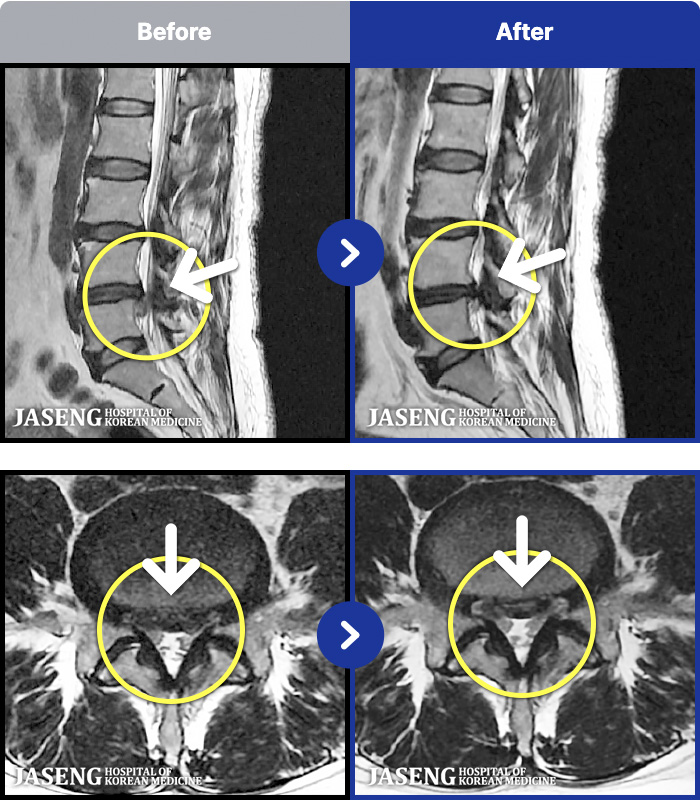

MRI ġ

MRI ũ ʸ Ȯϼ.